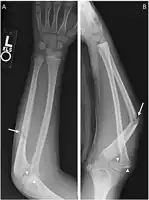

Monteggia fracture dislocation

Monteggia fracture

There are four types (depending upon displacement of the radial head):[3]

- I - Extension type (60%) - ulna shaft angulates anteriorly (extends) and radial head dislocates anteriorly.

- II - Flexion type (15%) - ulna shaft angulates posteriorly (flexes) and radial head dislocates posteriorly.

- III - Lateral type (20%) - ulna shaft angulates laterally (bent to outside) and radial head dislocates to the side.

- IV - Combined type (5%) - ulna shaft and radial shaft are both fractured and radial head is dislocated, typically anteriorly.